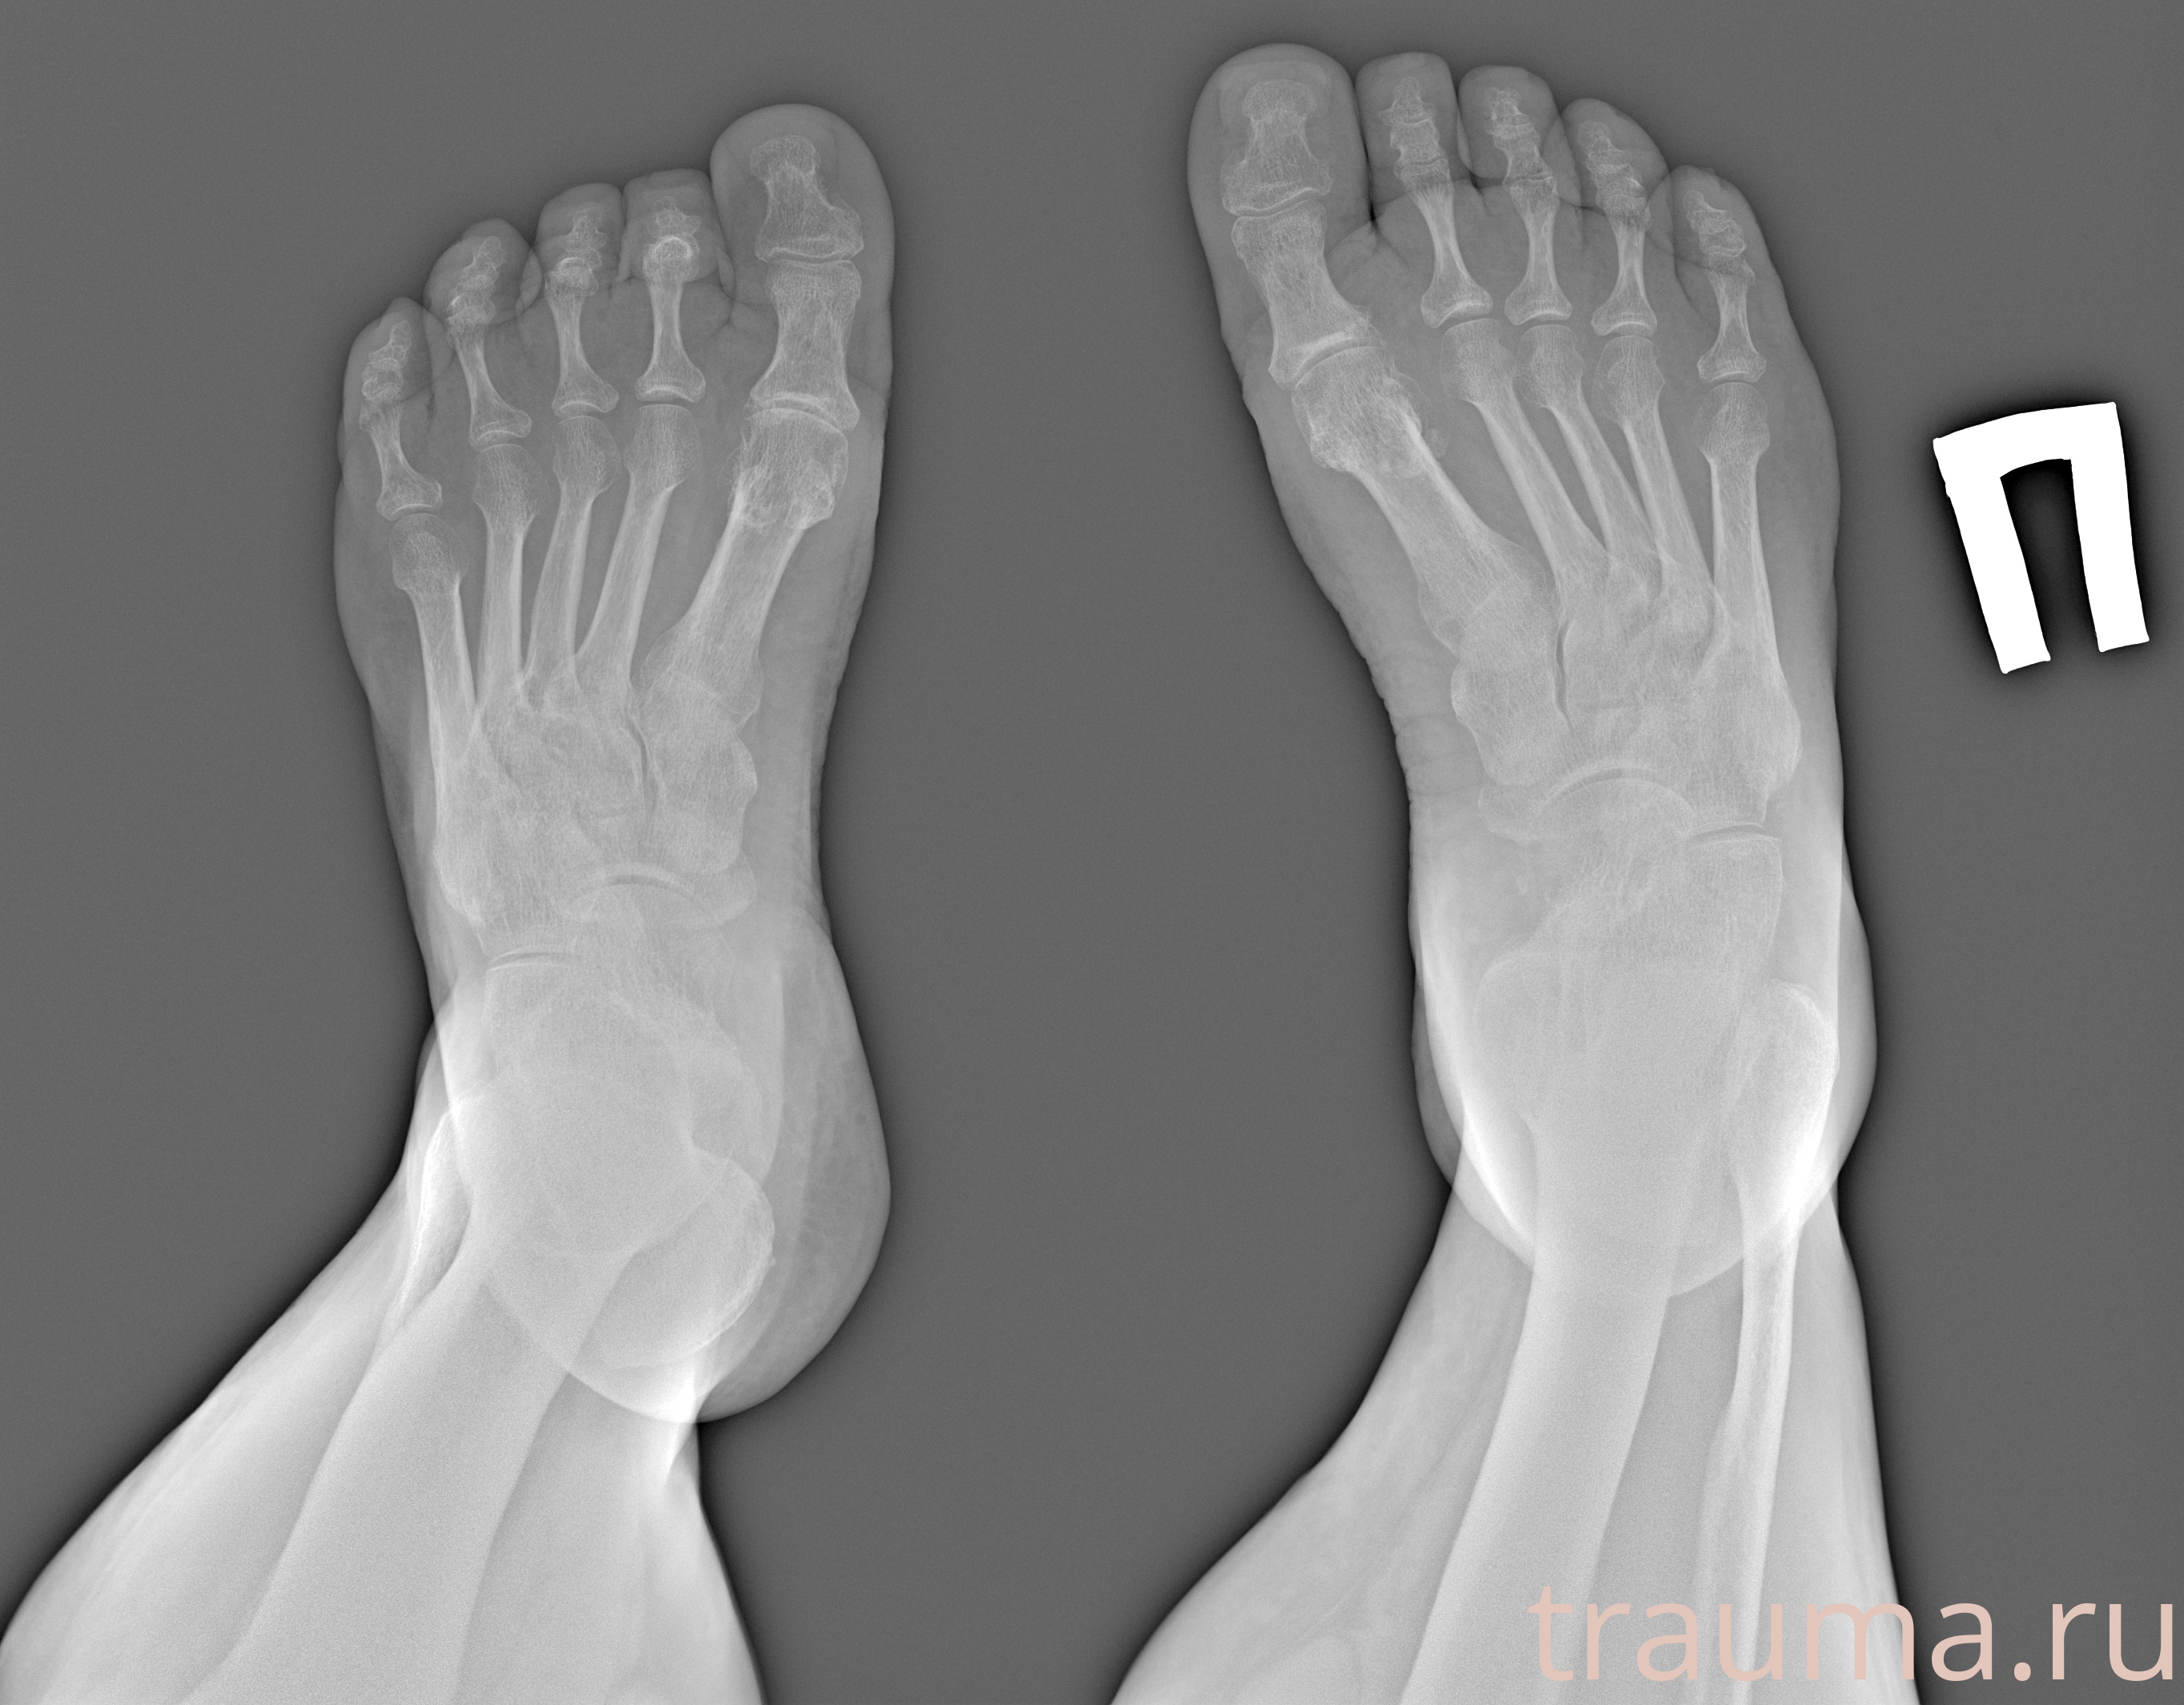

Рентген на дому: по вашему адресу приезжает врач-рентгенолог, травматолог-ортопед с мобильным рентгеновским аппаратом, проводит диагностику травмы или заболевания, делает необходимые рентгенограммы, дает рекомендации по дальнейшему лечению. Получить качественные снимки в домашних условиях возможно благодаря уникальной методике, разработанной МосРентген Центром для института  Склифосовского